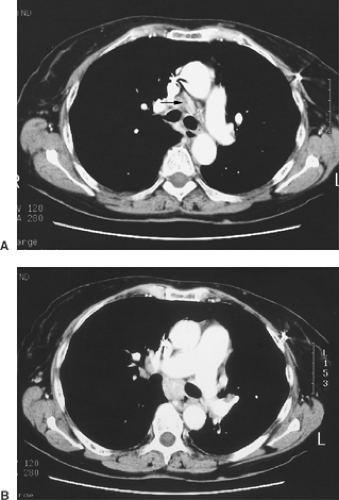

Mediastinal Sarcoid Like Reaction In Cancer Patients Pulmonology from multimedia.elsevier.es Assess the lymph node's borders to determine if they feel regular or irregular. Lymph nodes are tender and hot. Also usually surrounded by giant cells and a rim of lymphocytes. With the exception of the central nervous system (cns), lymph nodes may be found in every area of the body. Helpful diagnostic features include presence and type of necrosis; In many cases of sarcoidosis granulomas of varying ages may be present. Microscopically there are mainly polys in the germinal centers. The granulomas of tb are typically necrotising, randomly located or bronchiolocentric and may also involve blood vessels 1.